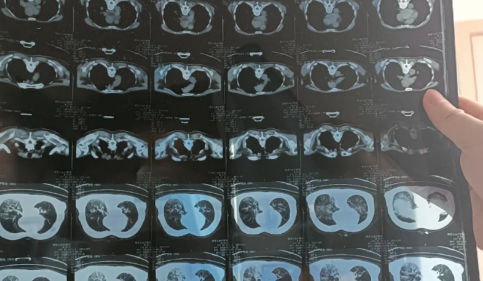

84岁老人肺全白有救吗

一般来说,84岁老人肺全白的话会比较难治,但不存在有没有救的说法。80岁老人肺部白,出现肺部感染的情况是比较难治好的,一般只能针对性进行治疗以控制病情。年高体弱治疗不及时者有可能会进一步发展为心、肺等等多器官的衰竭,甚至可能会出现昏迷、休克、死亡的严重后果。

新冠肺部白化能恢复吗

新冠肺部白化能不能恢复、能不能痊愈,要看症状的严重程度以及自身免疫力。如果是自身免疫力较强,且症状比较轻的,而又是得到及时治疗和有遵医嘱积极治疗的,这种情况下,新冠白肺是有可能会痊愈的,但也有可能会留下肺部纤维化的后遗症。